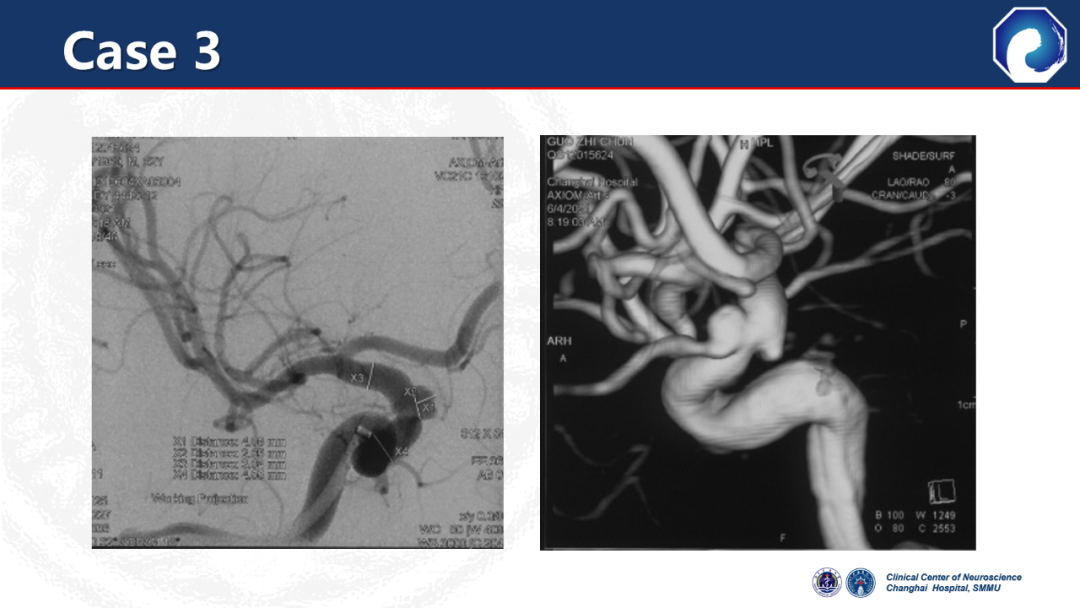

CASE 3

颈内动脉释放血流导向装置,通桥医疗银蛇®DA到达海绵窦段水平段;释放支架时,头端无移位。